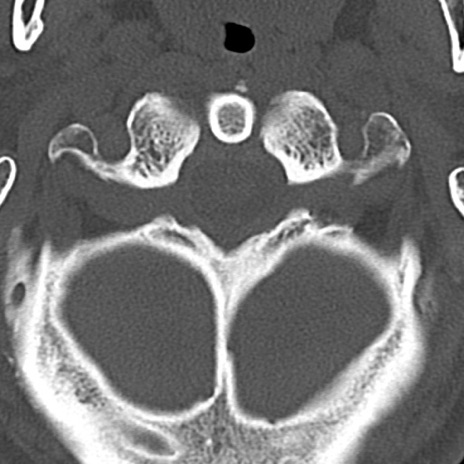

頚椎CT

横断像